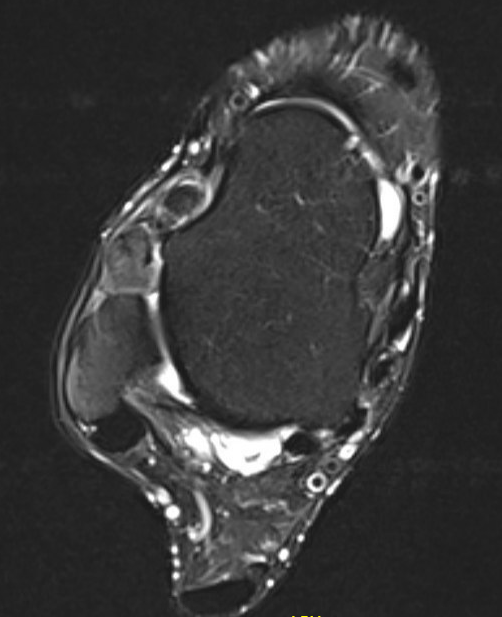

GCT flexor tendon sheath

GCT of tibialis posterior tendon sheath